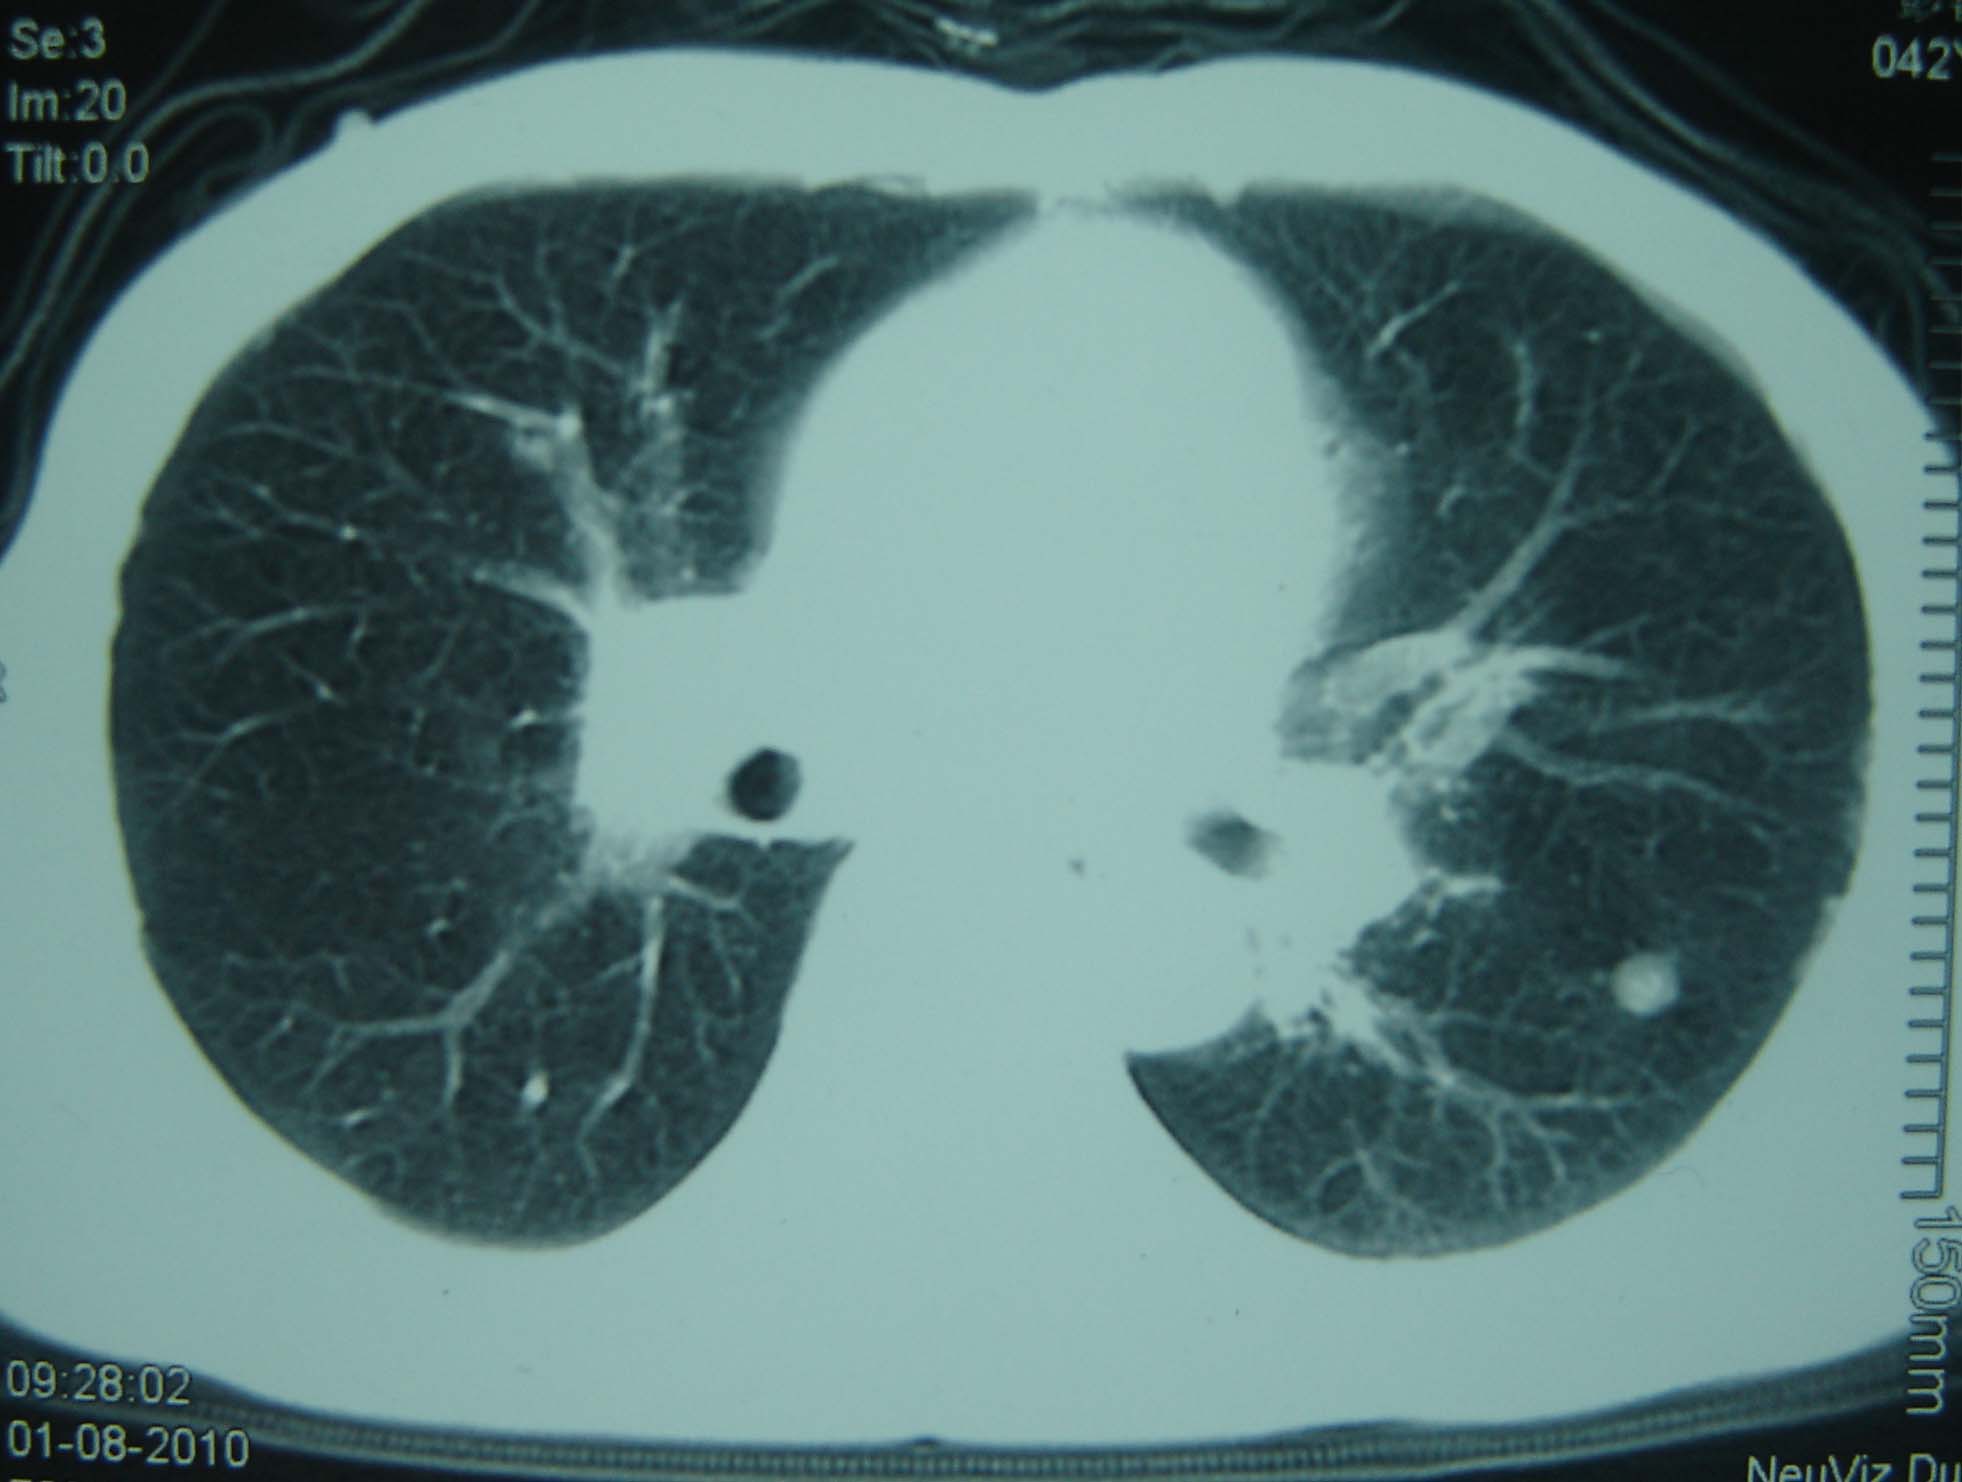

标题: CT25321:两肺多发结节 请会诊 [打印本页]

男 、43岁,咳嗽胸痛,装修工,平时接触粉尘较多,有吸烟史10多年,纤维支气管镜检查未发现异常,胃镜、腹部b超检查亦未发现异常,颈部淋巴结活检未发现肿瘤细胞。

不能排除转移,如果不能找到原发灶,只有短期随访。

结节病?转移瘤?

1)考虑双肺及胸膜多发性转移瘤。2)肺气肿。